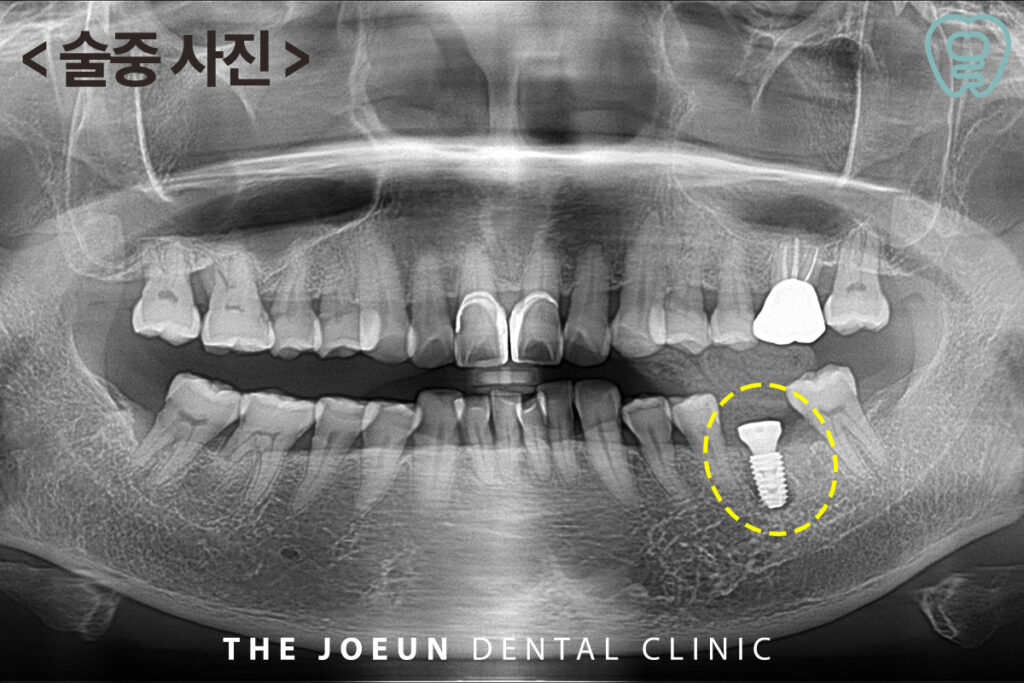

발치 후 치아 뿌리에 붙여 있는 염증 덩어리가 명확히 확인되었는데요. 잇몸뼈의 골질이 약하다고 판단되어 임플란트 식립 후 충분한 기간을 기다려준 뒤 최종 보철물을 진행하는 것으로 하였습니다.

발치 후 즉시 임플란트의 핵심은 충분한 골질과 정확한 식립인데요. 일반적으로 발치 부위의 골질이 일정 수준(D3 이상)을 충족하면 초기 고정을 확보하기엔 문제가 없어 시행이 가능하다고 알려져 있습니다. 따라서 전문 의료진과의 충분한 상담 후 진행하시는 것이 좋습니다. 이러한 조건이 갖추어진 상태라면 치료에 문제가 없지만 개개인의 구강 상태와 골 상태에 따라 달라질 수 있기 때문에 사전 정밀 진단은 필수적입니다.